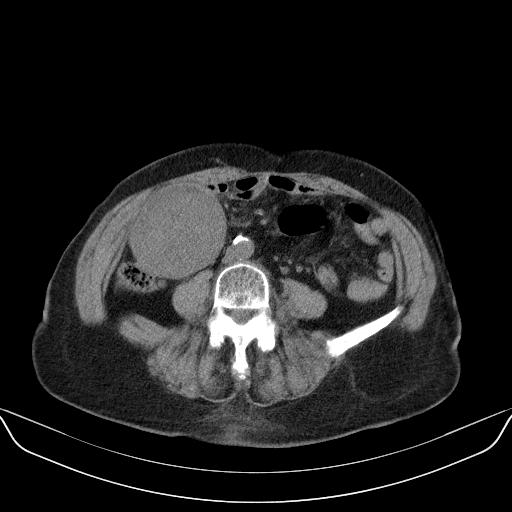

以下是引用yuhongjun在2010-3-12 6:32:00的发言:[br]回肠末端间质瘤,不除外阑尾粘液囊腺瘤,臀部注射性肉芽肿钙化. [br] [br]